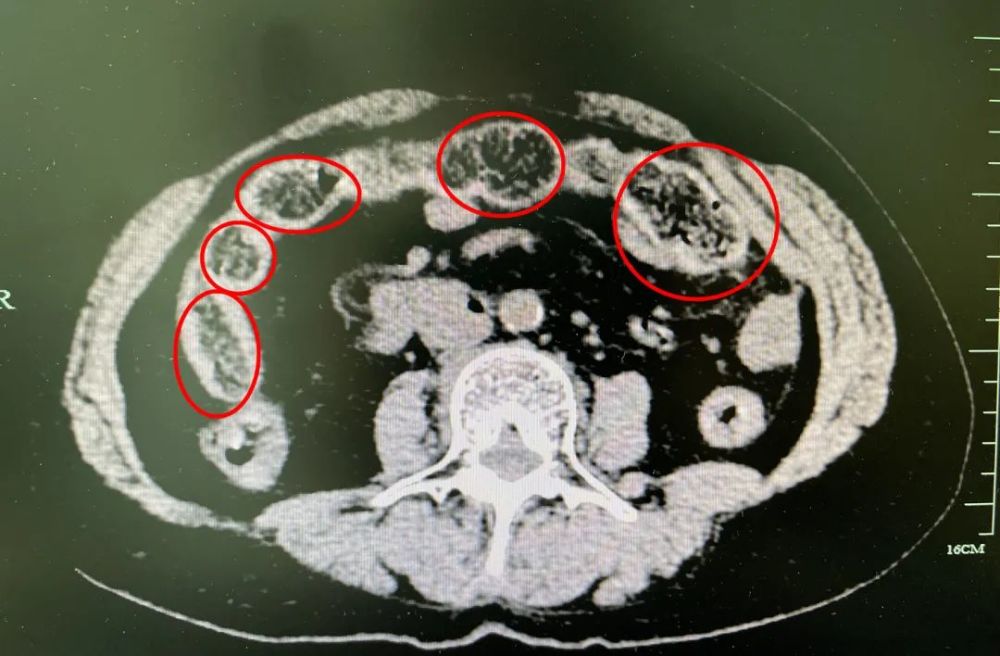

急性粪石性肠梗阻行小肠切开取粪石1例

图片尺寸4032x3024